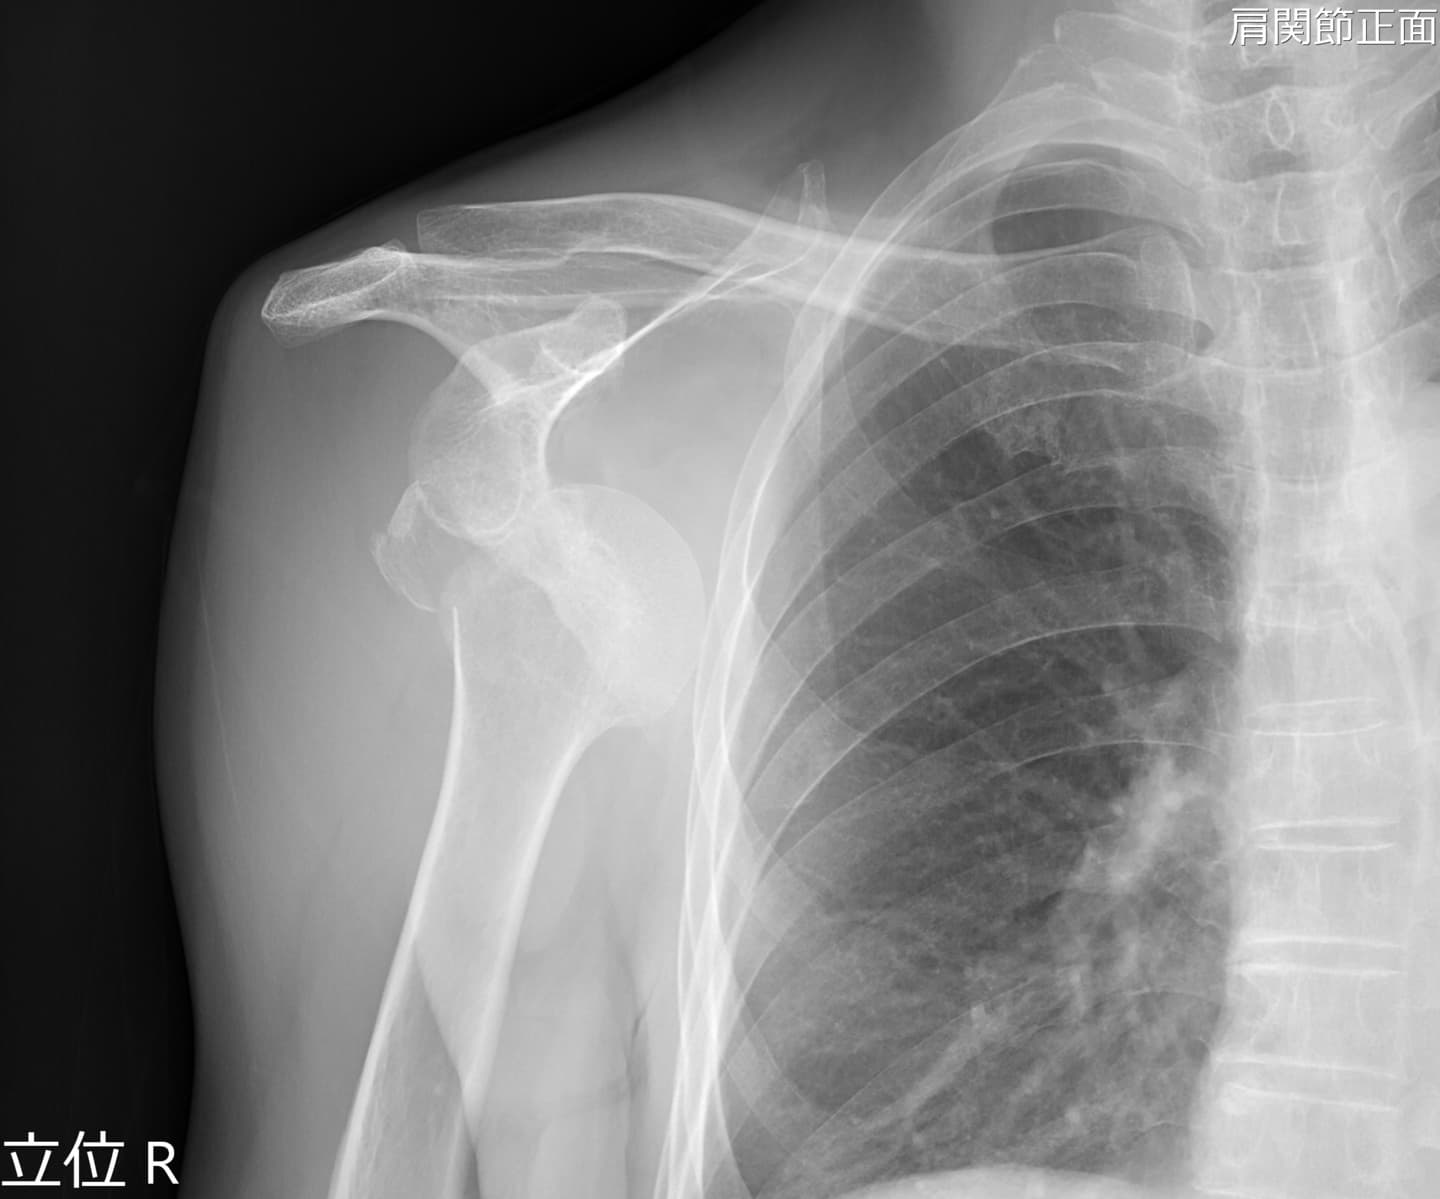

整形外科では、椎間板ヘルニアなどによる神経障害の痛みを軽減させる神経根ブロックなどの治療を行っています。また、脊髄腔や様々な関節腔(肩関節、股関節、手関節など)に造影剤を注入し、関節腔の形態を調べます。

寝台が広いため、骨折や関節脱臼をX線透視下で確認しながらの整復を行っています。

また、断層撮影が可能となっており、一度の撮影で骨の重なりを避けた高精細の画像を得ることができます。